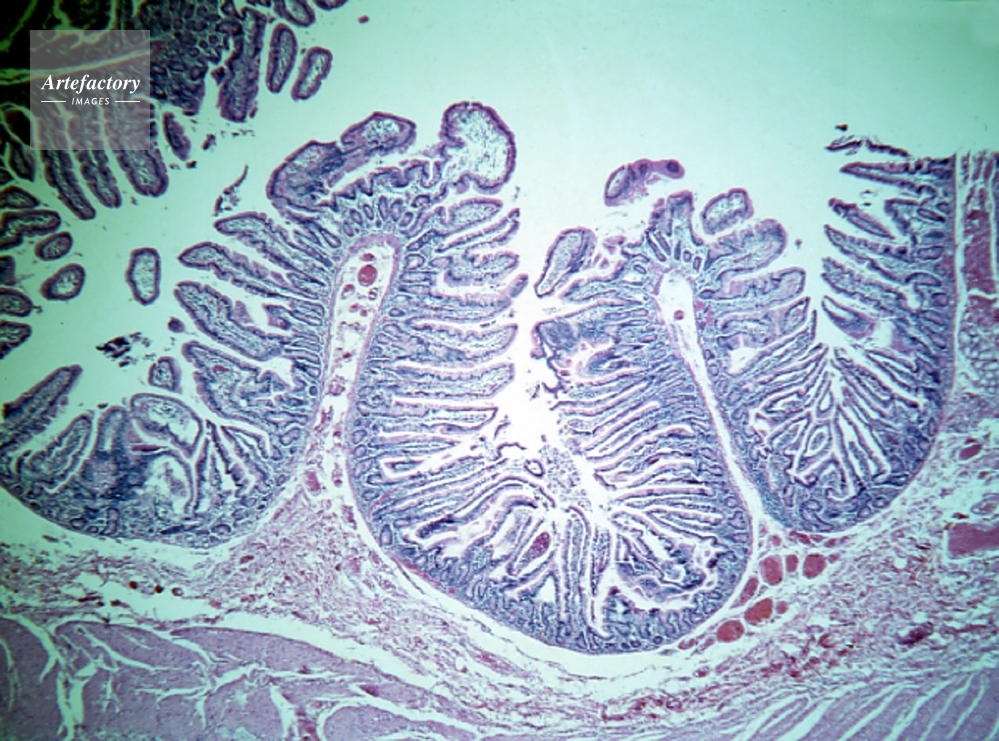

| 作品タイトル | 小腸(空腸)柔毛 | モデルリリース | なし | |

| キャプション | ヘマトキシリンエオシン染色、長辺55mmの場合 12倍 | 制限事項 | こちらはポジのみの画像です。貸出中につきご提供できない場合はご了承ください。 | |